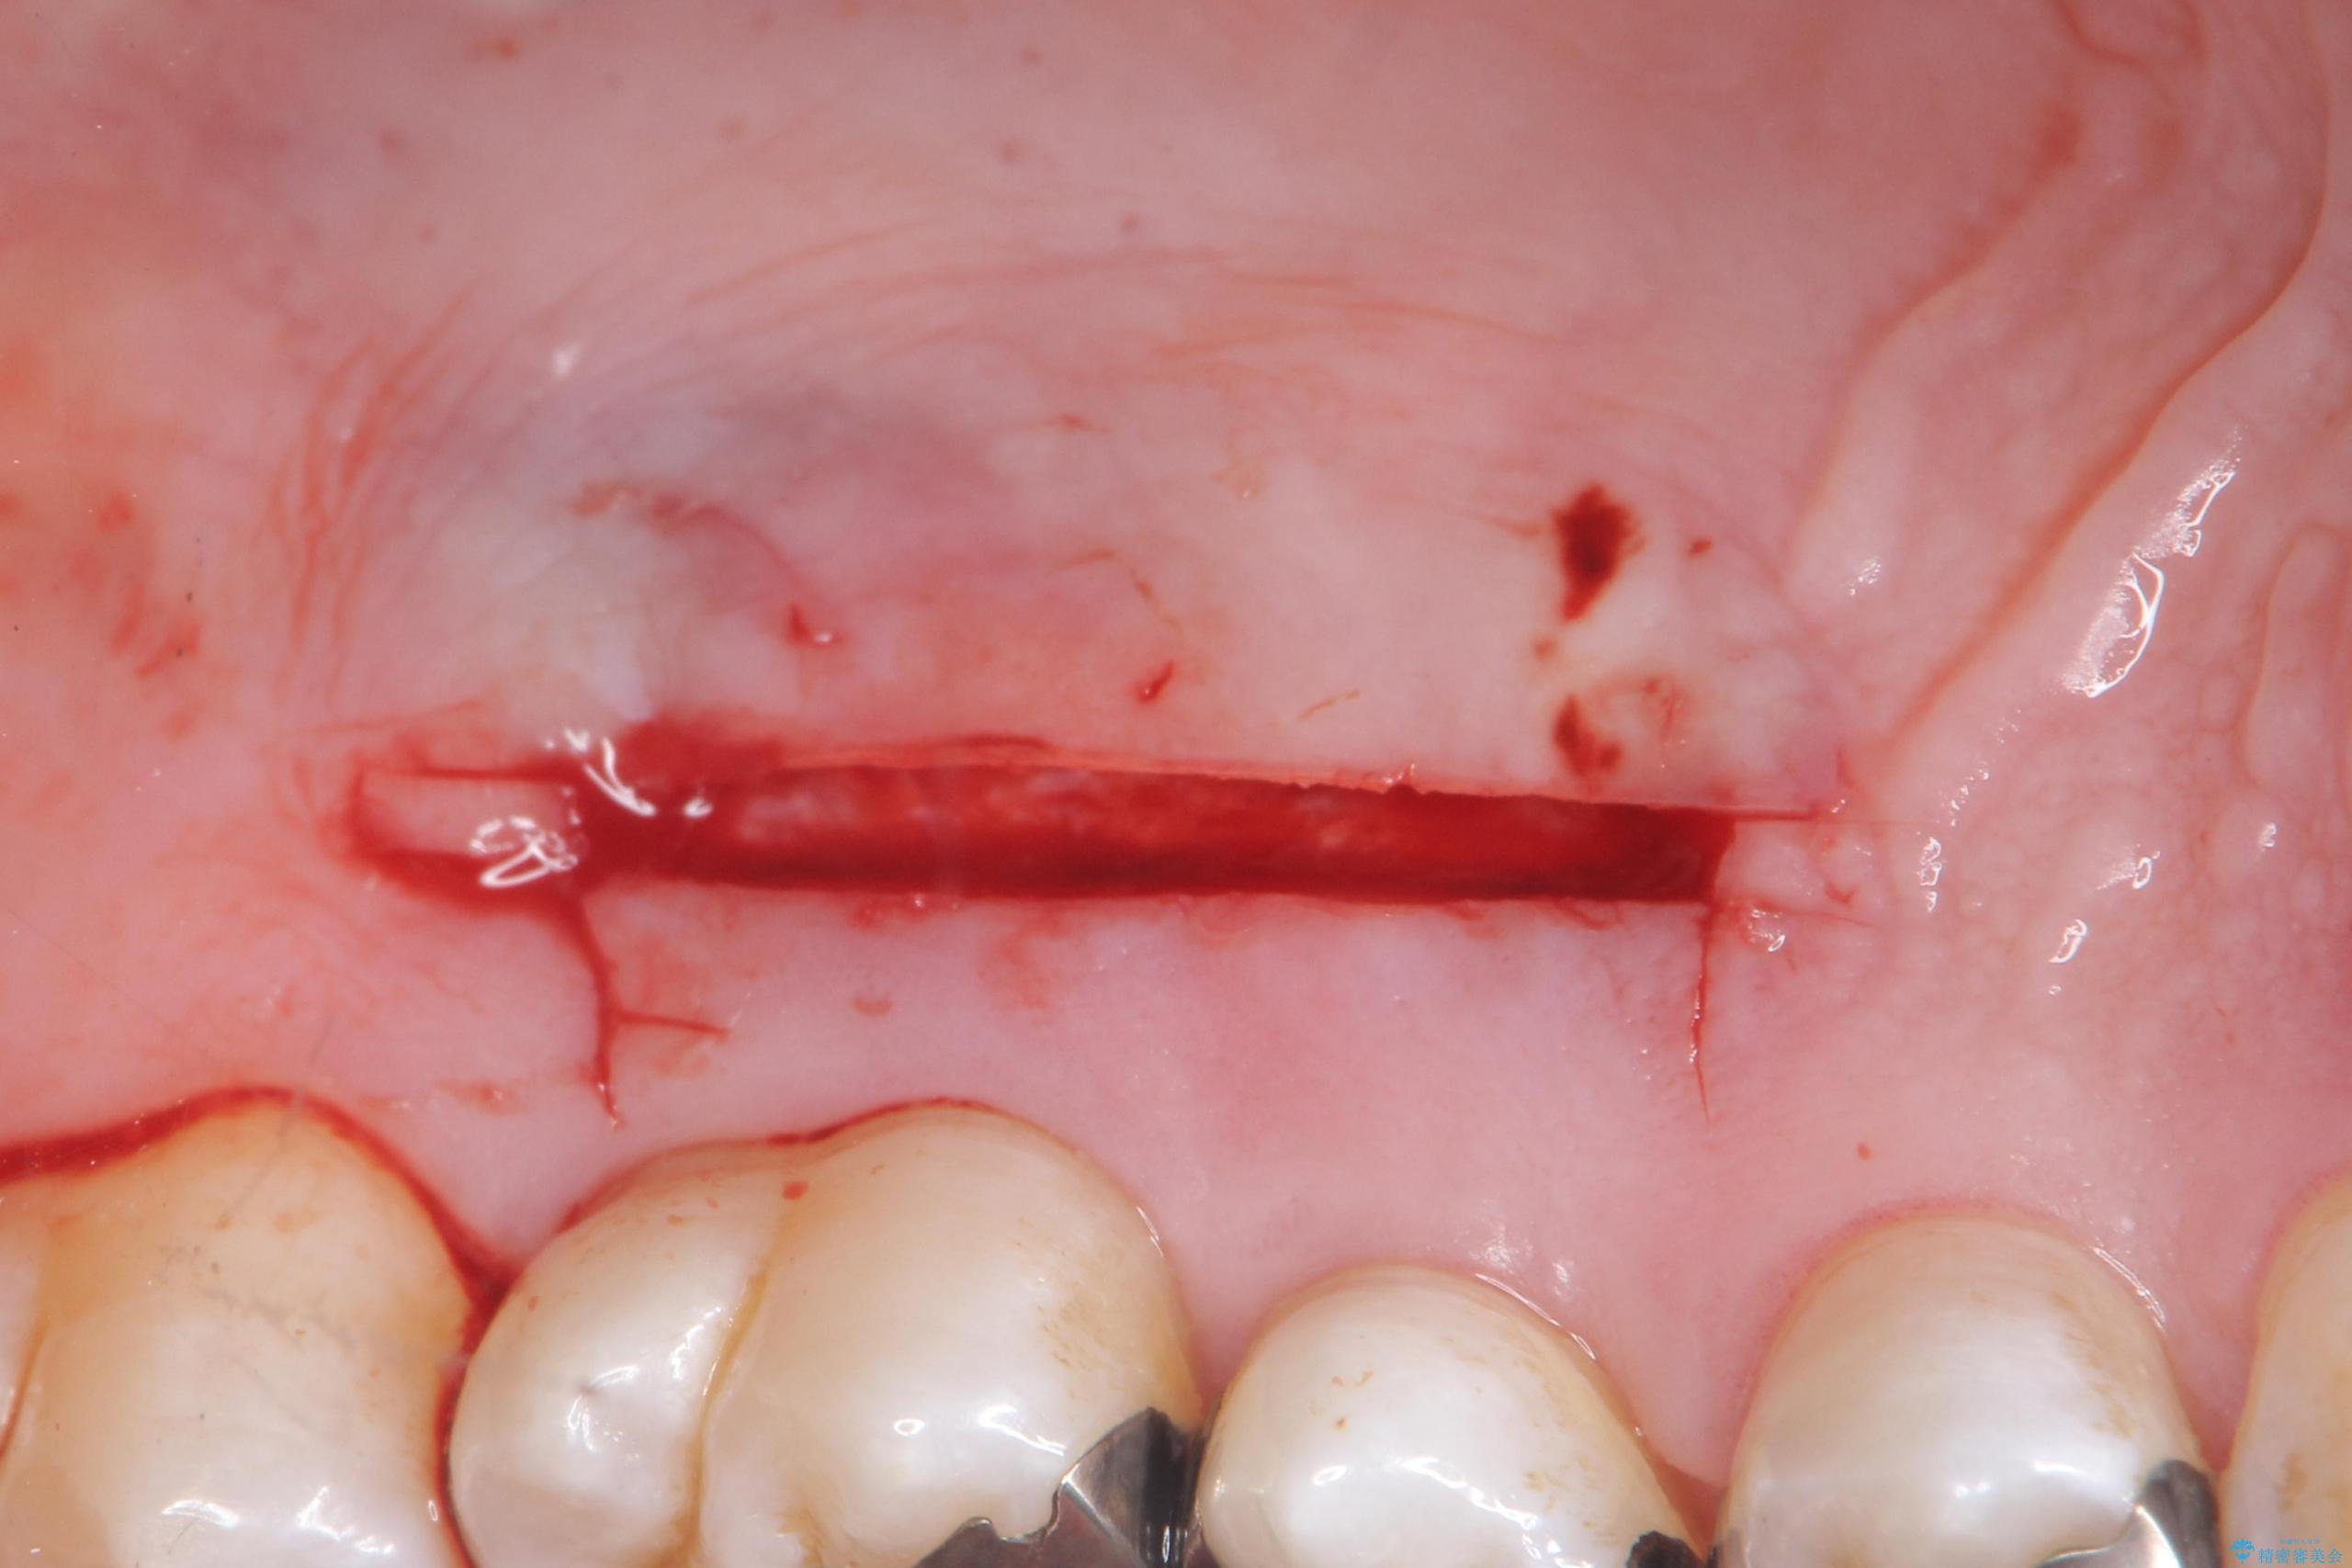

退縮した歯茎に対して移植をすることで、しみる場所を覆う計画です。

歯根の分岐部よりも根尖側の頬側面が露出している状態でしたが、露出部位を分岐部までに抑えることができました。